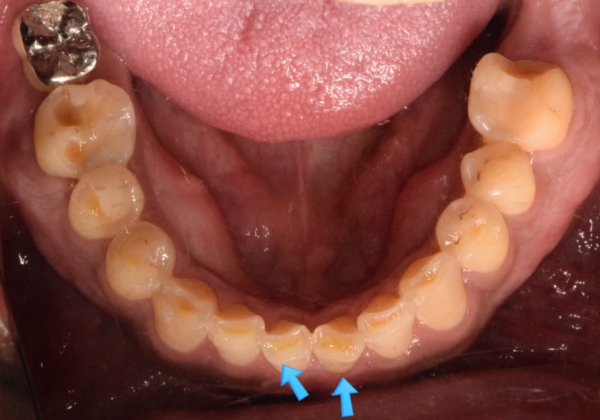

이 환자분은 이가 너무 시린증상이 있어서 저희 모란역 더서울치과를 찾아오셨습니다.

시린니의 원인은 다양할 수 있지만, 이 환자분은 치아를 보면 이갈이가 원인인것을 쉽게알 수 있습니다.

치아의 단면이 일정하게 갈려져있는것이 관찰되기 때문입니다.

이 환자분은 치아의 가장 단단한 겉면인 법랑질이 거의 마모되어있습니다.

이정도로 상아질이 드러나면, 이가 상당히 시리게된답니다.